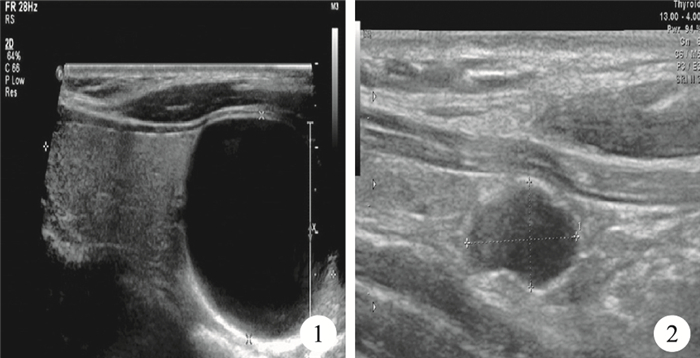

6例患者術前均行超聲檢查(表 1),其中4例提示甲狀腺左葉囊腫(圖 1);1例提示甲狀腺左葉下極下方低回聲團(圖 2);1例提示甲狀腺右葉結節伴微小鈣化灶,甲狀腺左葉下極下方囊性包塊。2例行甲狀腺ECT檢查,1例顯示甲狀腺左葉下極“冷”結節,1例顯示甲狀腺雙葉核素分布不均勻。術前診斷見表 1。

示甲狀腺左葉下極囊性腫物(30 mm×29 mm),邊界清楚,內呈液性??圖 2 ??示甲狀腺左葉下極下方低回聲團(10 mm×6 mm),邊界清楚,形態欠規整

Ultrasonography image showed a cyst (30 mm×29 mm) in the left lower thyroid lobe, with clear boder ??Figure 2?? Ultrasonog-raphy image showed a low echo mass (10 mm×6 mm) inferior to the left lower thyroid lobe, with clear boder and irregular shape